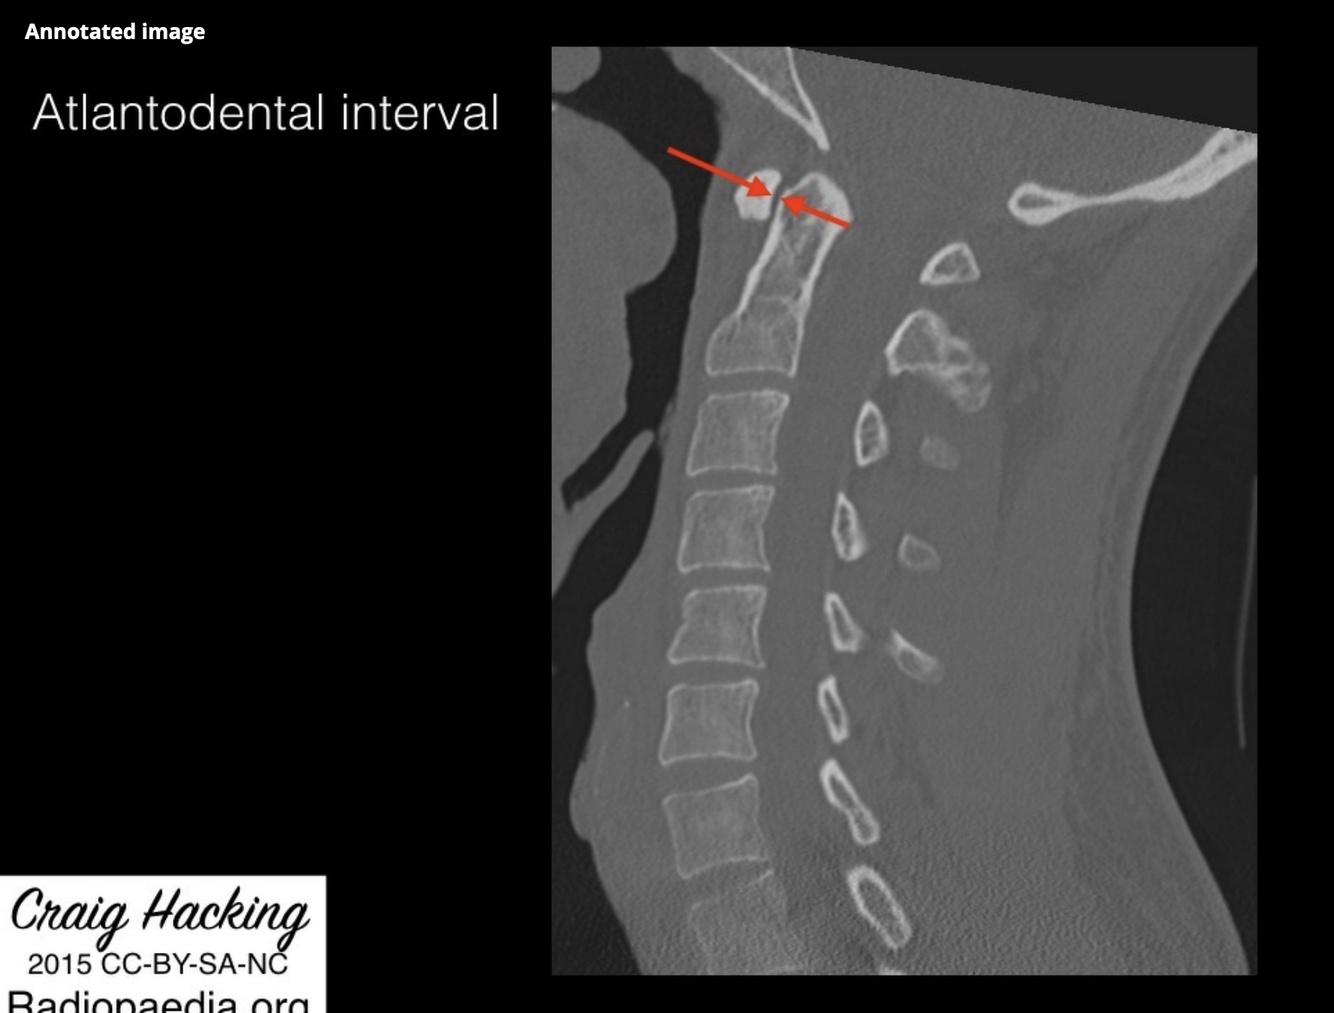

Patients with rheumatoid arthritis and the most common form of atlantoaxial instability have a widened atlantodental interval. This is measured between the

A. distance from posterior surface of dens to anterior surface of posterior arch of atlas

B. distance from anterior surface of dens to anterior surface of posterior arch of atlas

C. distance from posterior surface of dens to anterior surface of anterior arch of atlas

D. distance from posterior surface of dens to posterior surface of posterior arch of atlas

E. distance from anterior surface of dens to posterior surface of anterior arch of atlas

Repeat 23.1

The atlantodental interval is used in the diagnosis of atlanto-occipital dissociation injuries and injuries of the atlas and axis.

The anterior atlantodental interval is the horizontal distance between the posterior cortex of the anterior arch of the atlas (C1) and the anterior cortex of the dens in the median (midsagittal) plane

Normal values for anterior atlantodental interval are:

radiographs:

adults:

males: <3 mm

females: <2.5 mm 1 (although most authors describe <3 mm ref)

children:

<5 mm ref

CT: adults: <2 mm